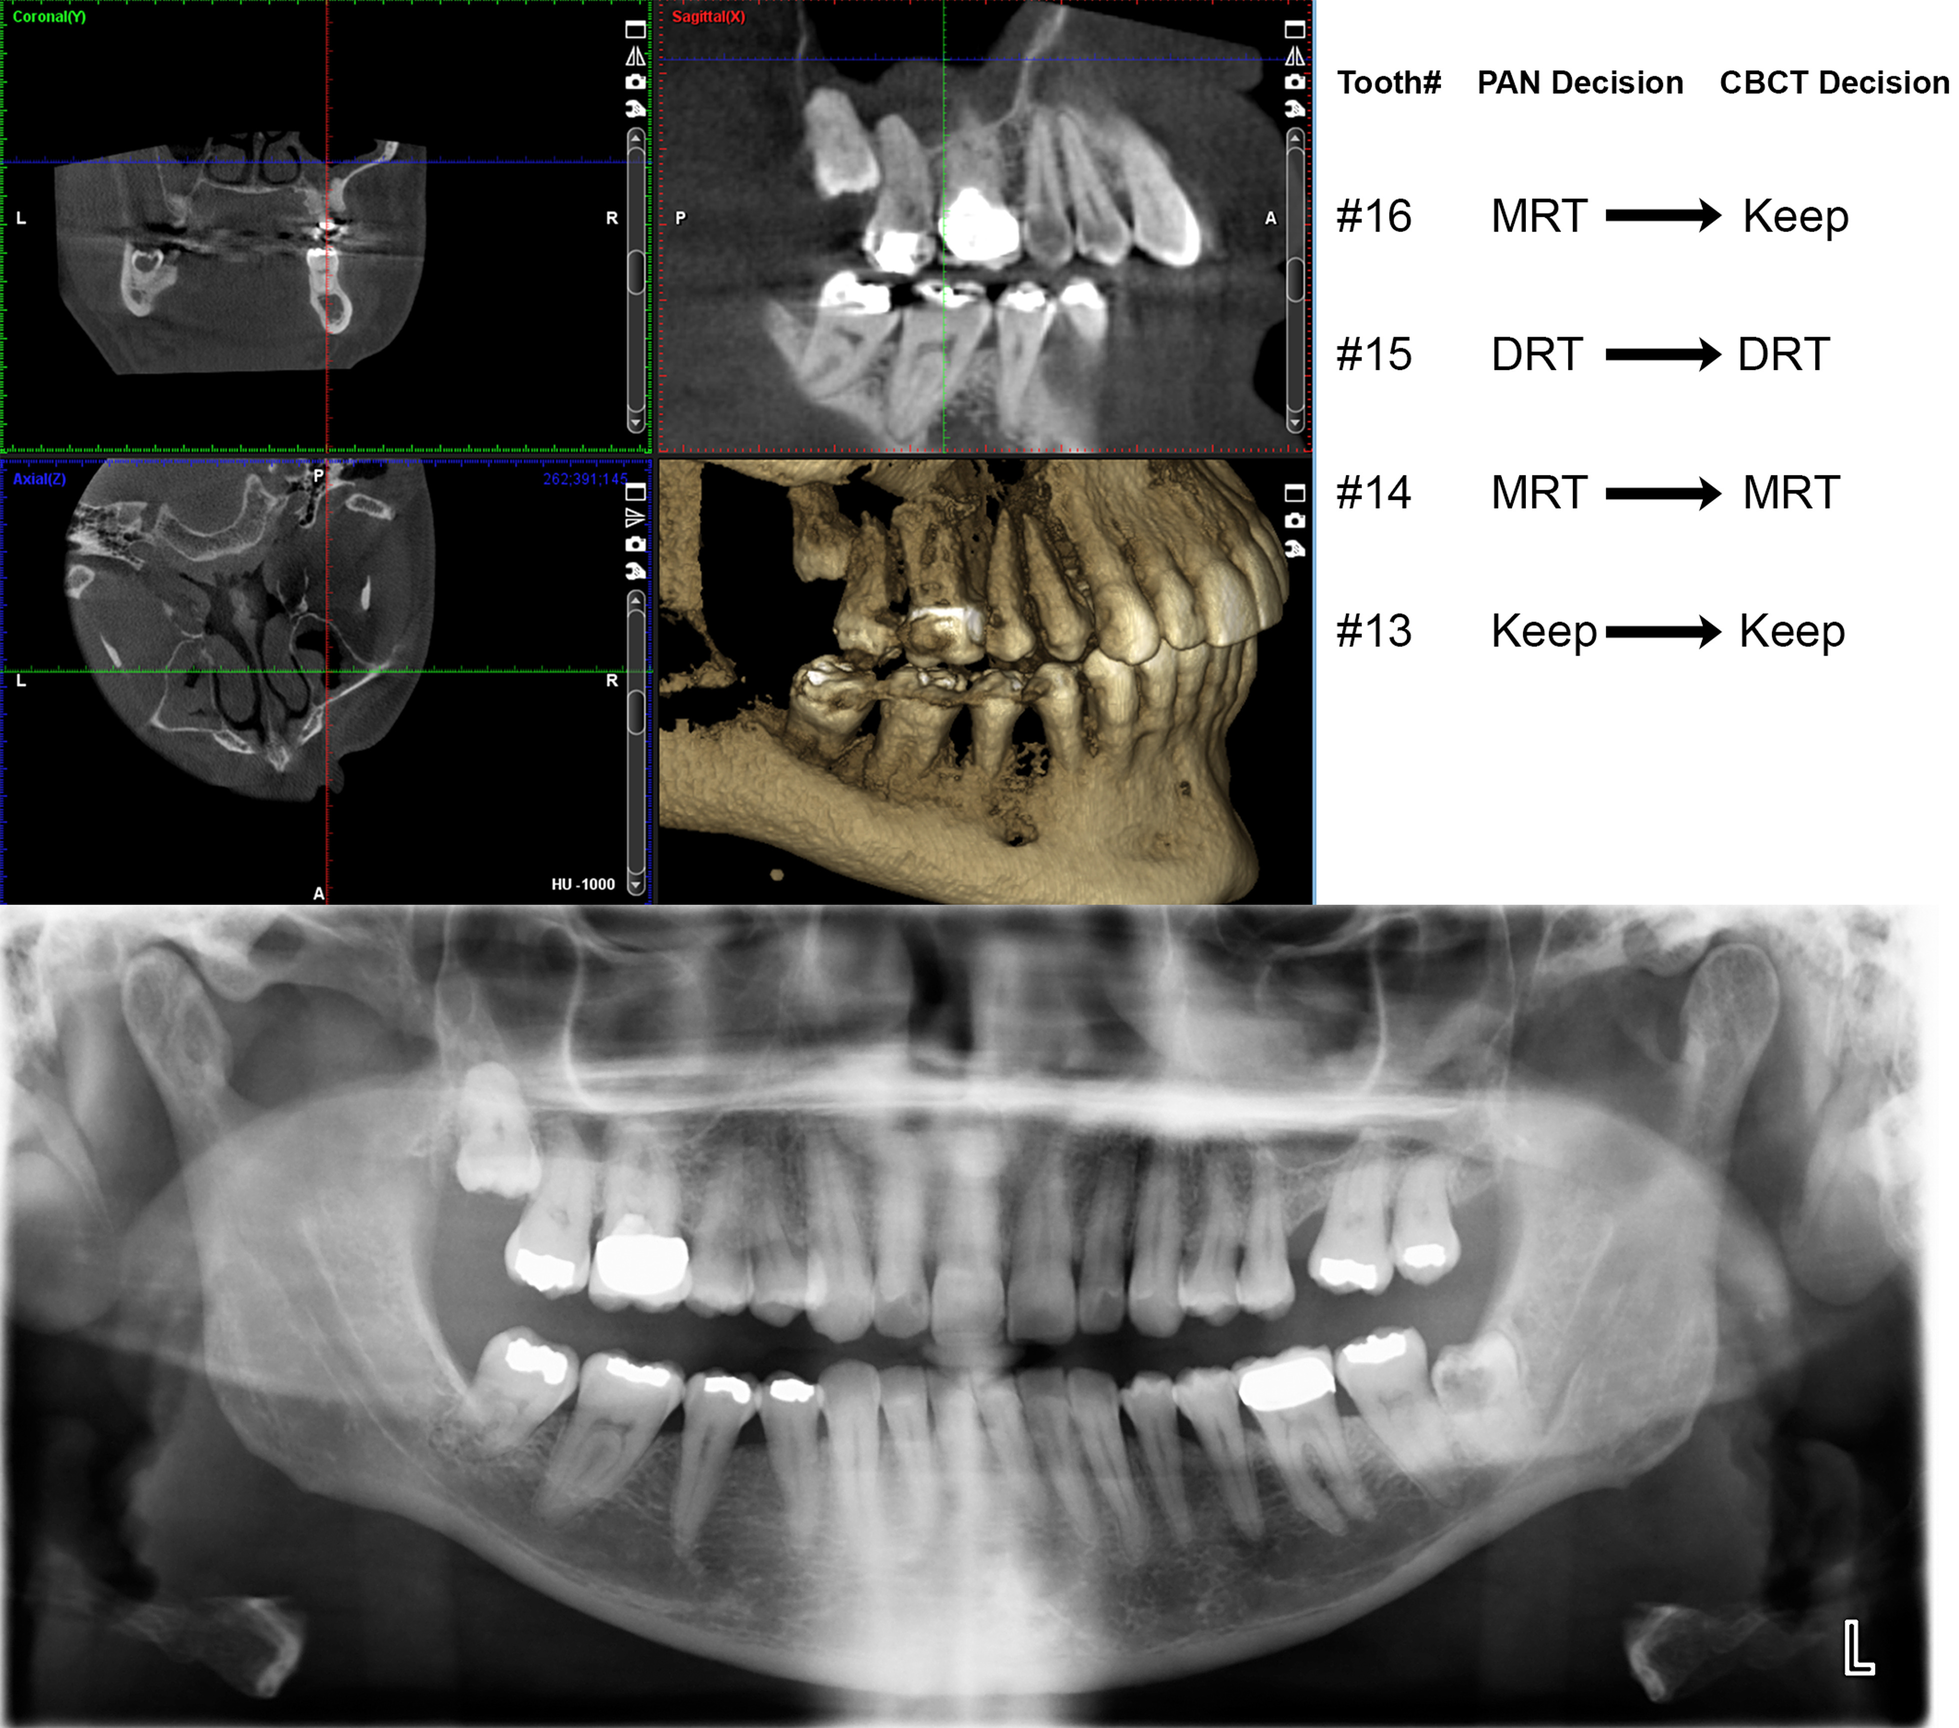

Fig. 2

An example of repositioning decisions made by examiner 1 for the upper right quadrant of displayed CBCT and PAN images are shown on the upper right portion of the figure. The CBCT view displaying right side teeth with focus on the upper right quadrant is shown on the top left side of the figure. The corresponding PAN image is displayed on the bottom of the figure